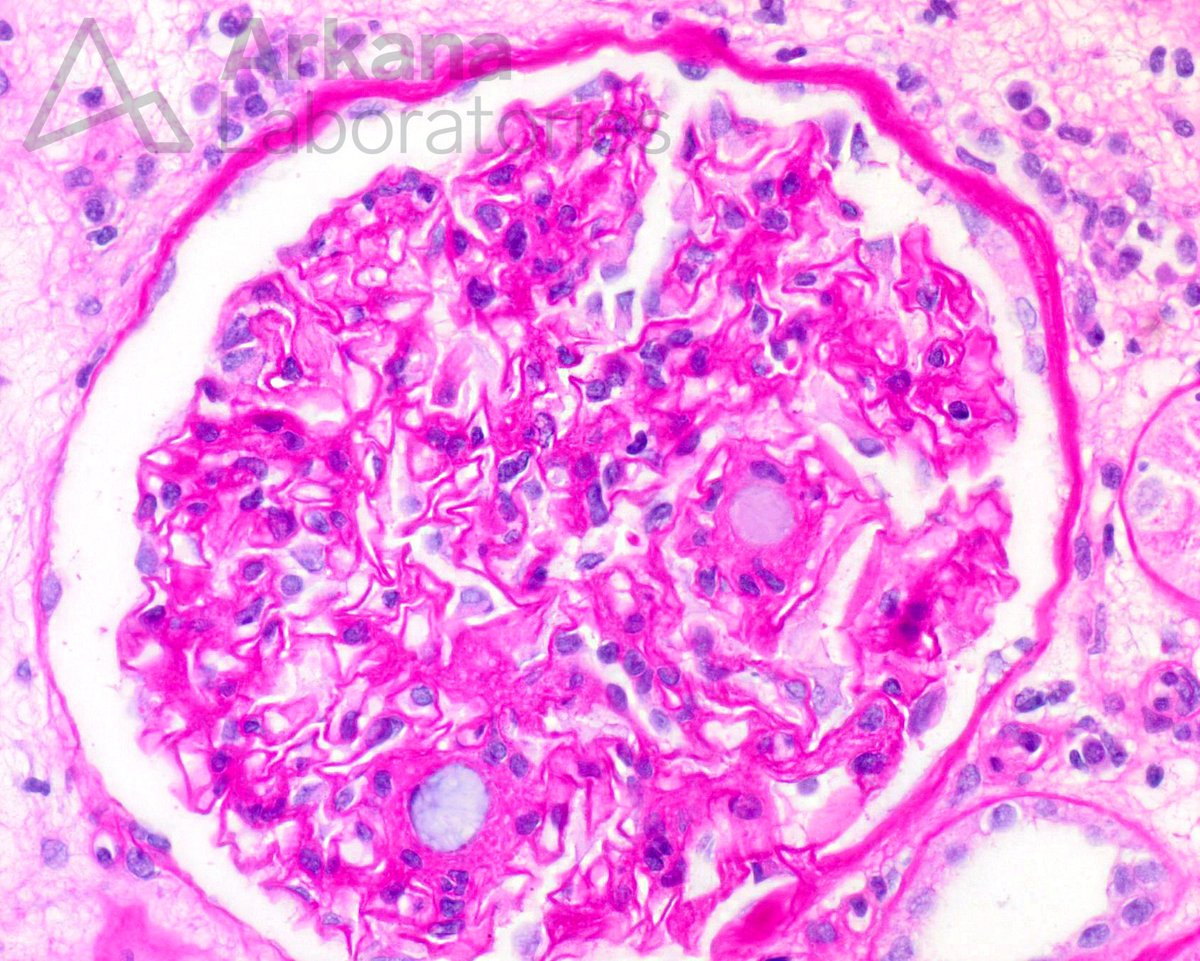

In a renal transplant recipient, what is your diagnosis? #NephTwitter #renalpath

arkanalabs's tweet image. In a renal transplant recipient, what is your diagnosis?

#NephTwitter #renalpath